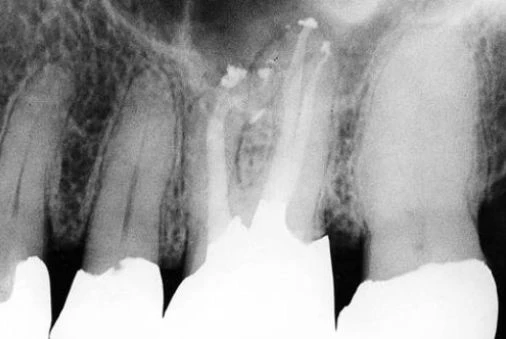

Hình 5.41. A. Phim X-quang trước điều trị của răng cửa giữa hàm trên bên phải. Lỗ chóp nằm trên cùng một mặt phẳng trên đường đi của tia X: nó có thể đối diện với mặt trong hoặc mặt ngoài. B. Phim X-quang thứ hai chụp theo hướng gần-xa cho thấy đoạn cong đối diện với mặt ngoài. Việc điều trị tủy được hoàn tất, giữ nguyên góc chụp cho phép nhìn thấy được điểm cuối cùng trên X-quang của ống tủy. C. Phim sau điều trị. Lưu ý rằng chỉ với góc chụp này mới thấy được hình ảnh tổn thương nhỏ tại chóp chân răng. D. Phim sau điều trị được chụp theo tiêu chuẩn hình chiếu. Lưu ý rằng vật liệu trám ống tủy dường như bị ngắn đi chừng 2mm và tổn thương cũng đã lành.